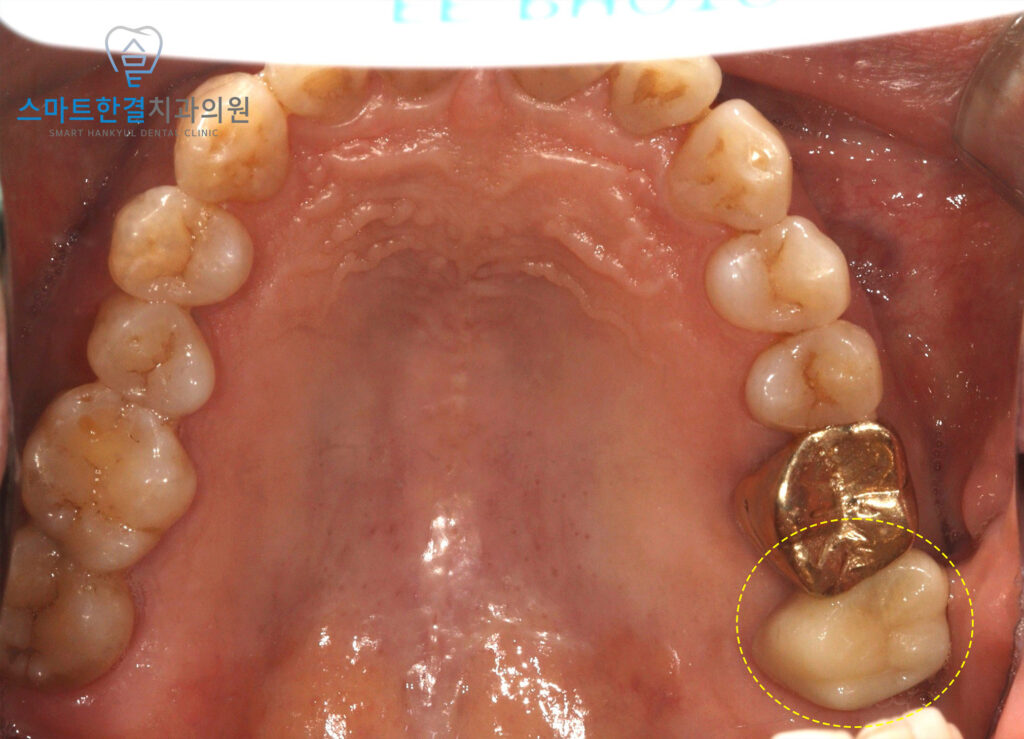

26.01

먼저 신경치료를 진행하여

내부 감염 부위를 소독하고 세척한 후,

근관 충전을 통해 치아 내부를

완전히 밀봉하여 감염이

재발하지 않도록 했어요.

근관 충전은 신경치료의 중요한 단계로,

치아 내부의 빈 공간을 적절히 채워

외부로부터의 추가 감염을 막고,

치아의 구조적 안정성을

유지하는 데 도움을 주는데요.

통증이 완화된 후,

치아의 기능을 회복하기 위한

보철 작업을 시작하였고

이는 치료의 마지막 단계로,

치아의 외형과 기능을 회복하는

중요한 과정이었어요.

25.09 / 26.01

화서동치과 스마트한결치과의

신경치료 전후 사진이에요.